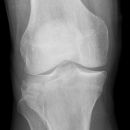

Gonarthrose